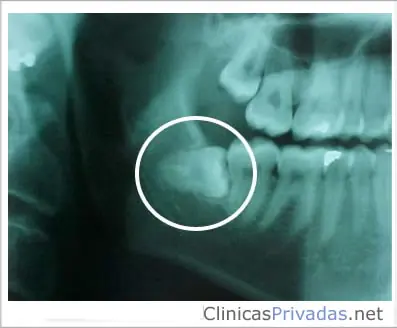

Las muelas del juicio

Solo el 5% de la población cuenta con un juego sano de estos terceros molares. Algunos podrían pensar que se les denomina “muelas del juicio” por las terribles molestias que provocan, pero no es así. A las cordales o terceros molares se les conoce tradicionalmente como “las muelas del juicio”, porque aparecen cuando una persona está ingresando a su etapa adulta (entre los 15 y 25 años de edad), y supuestamente es cuando posee “más juicio” o sentido común. Se cree que estos cuatros molares se desarrollaron hace miles de años cuando el ser humano necesitaba de una masticación más fuerte, pues su alimentación era principalmente a base de alimentos crudos. Extraer una muela de juicio es el procedimiento más común que realizan los dentistas.